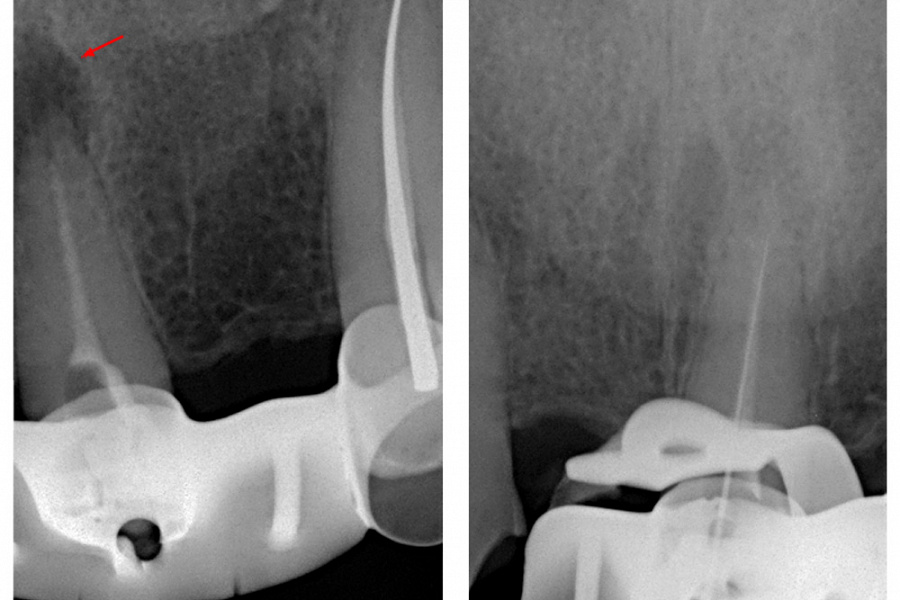

Выявлена болезненность при перкуссии и пальпации в области 21 зуба. Зуб не реагирует на термические раздражители. Результаты пародонтологического обследования в пределах нормы, рентгенологическое обследование выявило радиолюцентную зону в области верхушки корня (снимки 1, 2).